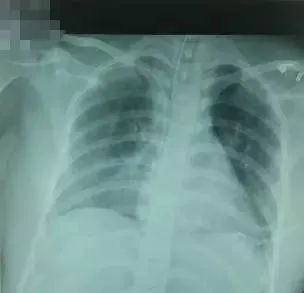

入院诊断“癫痫、休克、猝死、代酸合并呼酸、肝功能不全”。当时气管插管距门齿为23cm,次日凌晨拍胸片出现左肺不张(图1),但漏诊,未作出处理。

图1 ?胸片显示气管插管尖端位于第5胸椎水平致左全肺不张